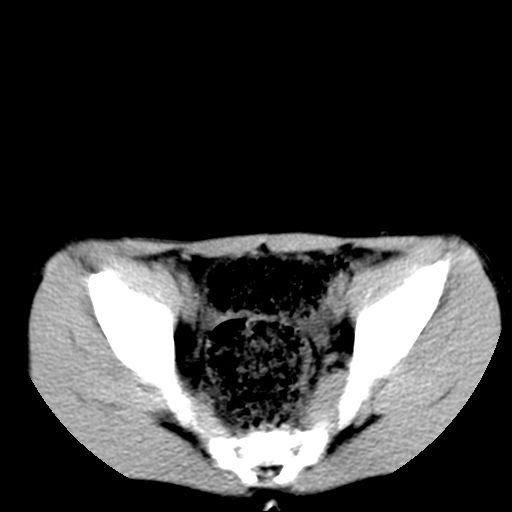

腹部好象未见异常。

腹部ct平扫未见明确异常

腹部ct平扫不能提示哪里有病变。